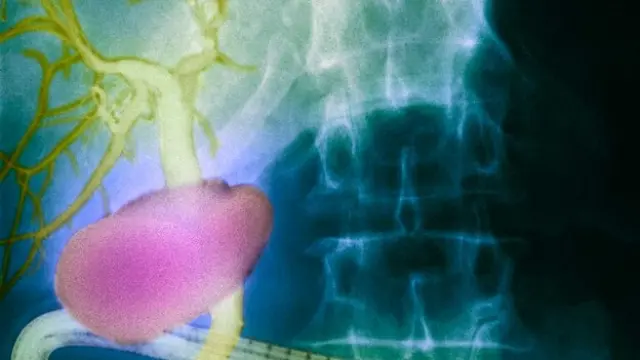

El patólogo Neil Theise y su equipo de la Escuela de Medicina de la Universidad de Nueva York aseguran haber descubierto un nuevo órgano del cuerpo humano, que además podría ser responsable de que las células cancerígenas se expandan por el cuerpo.

Este nuevo órgano humano es una red de canales microscópicos distribuidos por todo el cuerpo, que transportan hasta el 20% de todos los fluidos que hay en nuestro cuerpo.

Tras descubrir esta red de canales microscópicos que transportan hasta el 20% de todos los fluidos del cuerpo, el doctor Neil Theise realizó la misma orbservación en las capas internas de la naríz, y también los encontró allí. Según explica, esta red de canales recorre todo el cuerpo y "actúa como un amortiguador", protegiendo a los órganos de posibles golpes.

Por desgracia, también han comprobado que entre los fluidos que transportan estos canales, están las células cancerosas. "Podríamos estar ante un nuevo mecanismo de expansión del cáncer por todo el cuerpo, que no conocíamos", afirma el doctor Neil Theise.